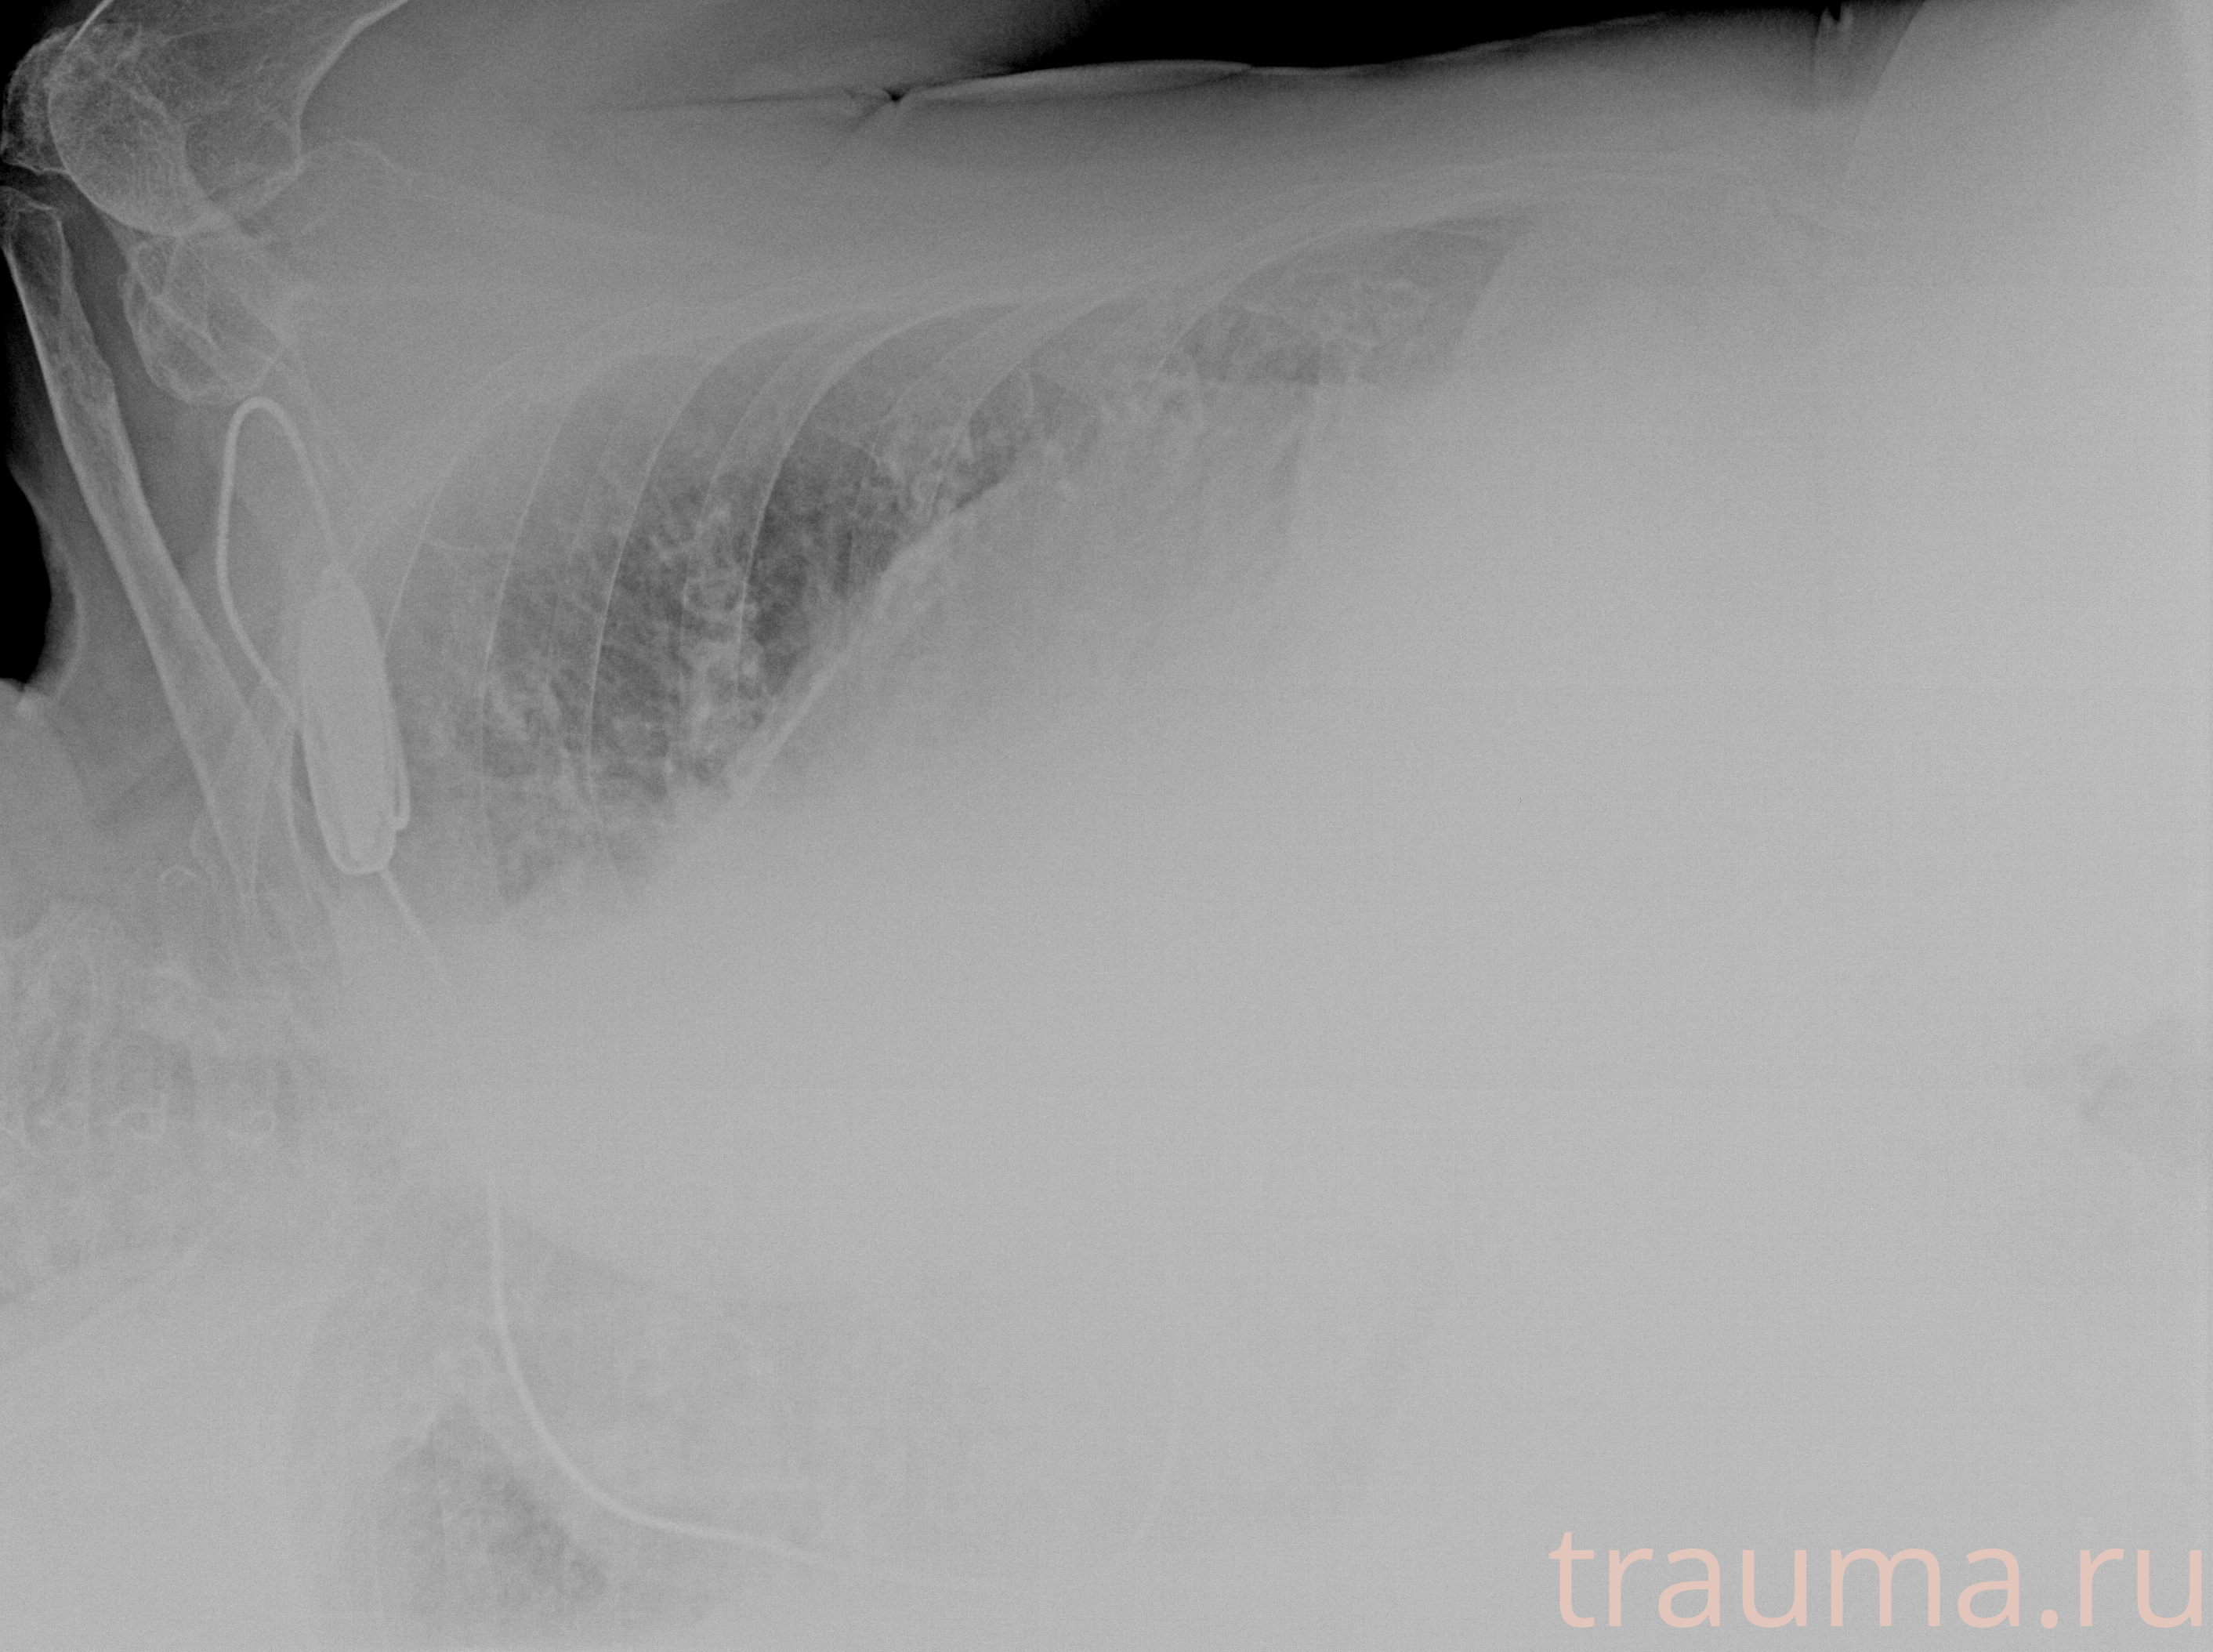

Рентгенограммы

Рентген на дому: по вашему адресу приезжает врач-рентгенолог, травматолог-ортопед с мобильным рентгеновским аппаратом, проводит диагностику травмы или заболевания, делает необходимые рентгенограммы, дает рекомендации по дальнейшему лечению. Получить качественные снимки в домашних условиях возможно благодаря уникальной методике, разработанной МосРентген Центром для института  Склифосовского

Яркость: 1   Контраст: 1   Инвертировать: 0 Увеличение: 1

Перетаскивайте мышь вверх/вниз для контраста, влево/право для яркости. Прокрутка колесом изменяет масштаб. Нажмите Сбросить для возврата к исходному изображению. При увеличении держите мышь в той области, которую хотите рассмотреть.

при переломе шейки бедра и пневмонии от компании МосРентген Центр - партнера Института имени Склифосовского